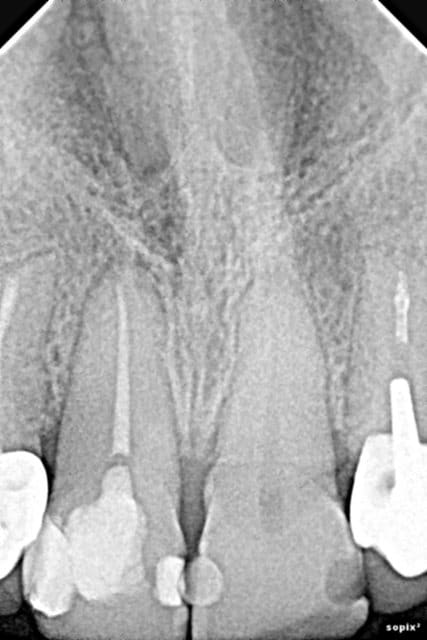

Moi j'aime pas l'apex de la 12... Préviens là quand même que ça peut ne pas durer si longtemps que ça pour cette dent. (idem 22)

Là est tout le problème... quel est l'avenir de ces dents antérieures ??

Est-ce que ça vaut le coup de les garder ? est-ce qu'on a 90% de chance que dans 5 ans la moitié soient à extraire...

Certaines des dents antérieures me paraissent courtes (la 22 en particulier): serait-il possible de les mesurer avec le logiciel?

Sinon, je ne vois pas pourquoi il ne serait pas possible de les garder avec un traitement canalaire bien réalisé + IC + couronnes solidarisées.